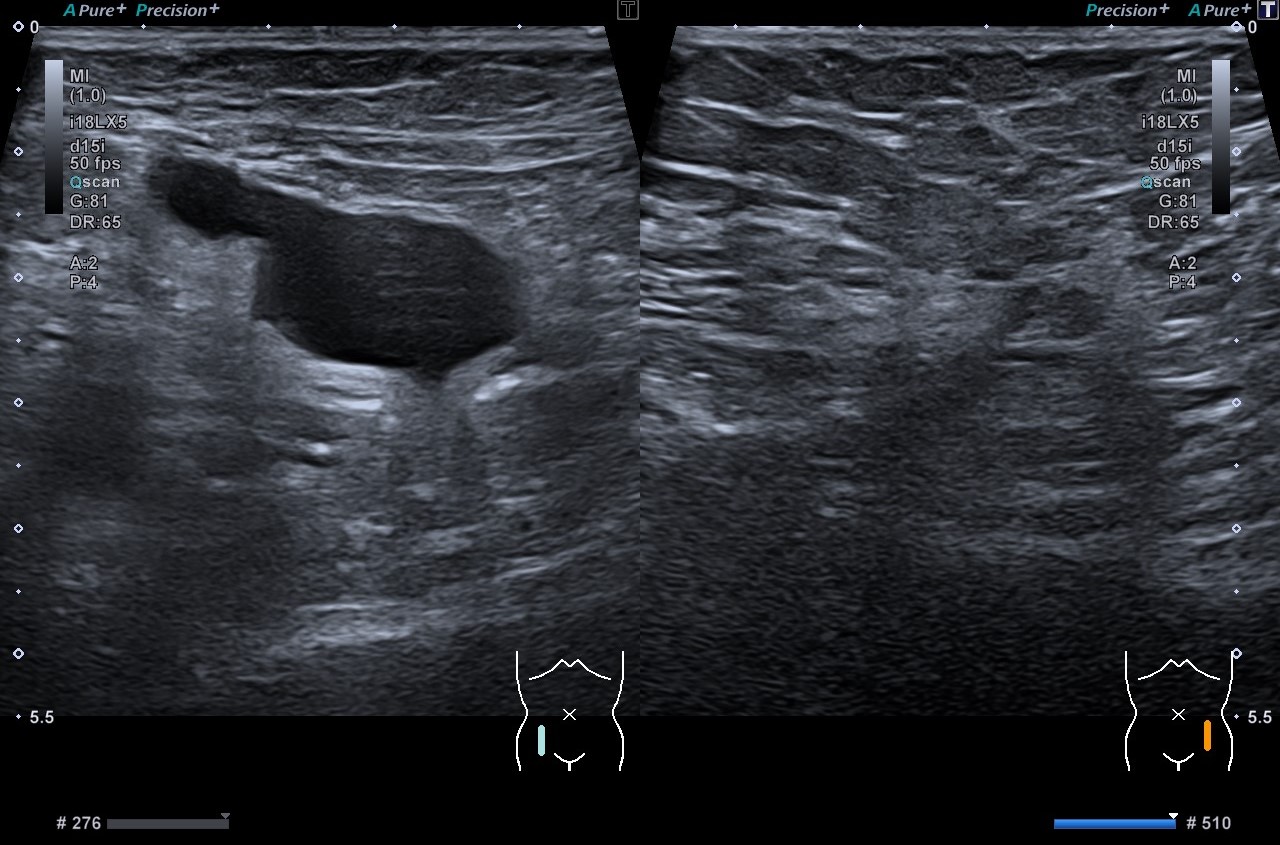

Se aprecia una colección líquida de unos 30 milímetros (mm) alargada con el extremo distal que termina en forma de pico en región inguinal derecha. Ecográficamente se aprecia ligera modificación con Valsalva.

Semanas después se realiza ecografía reglada por el radiólogo que describe una colección de unos 33 mm con morfología «en pico», que se modifica discretamente con Valsalva presentando un cuello de unos 7 mm. Impresiona de imagen compatible con una hernia inguinal con contenido líquido aunque su morfología peculiar recuerda al quiste de Nuck, que resulta excepcional en el rango de edad de la paciente.